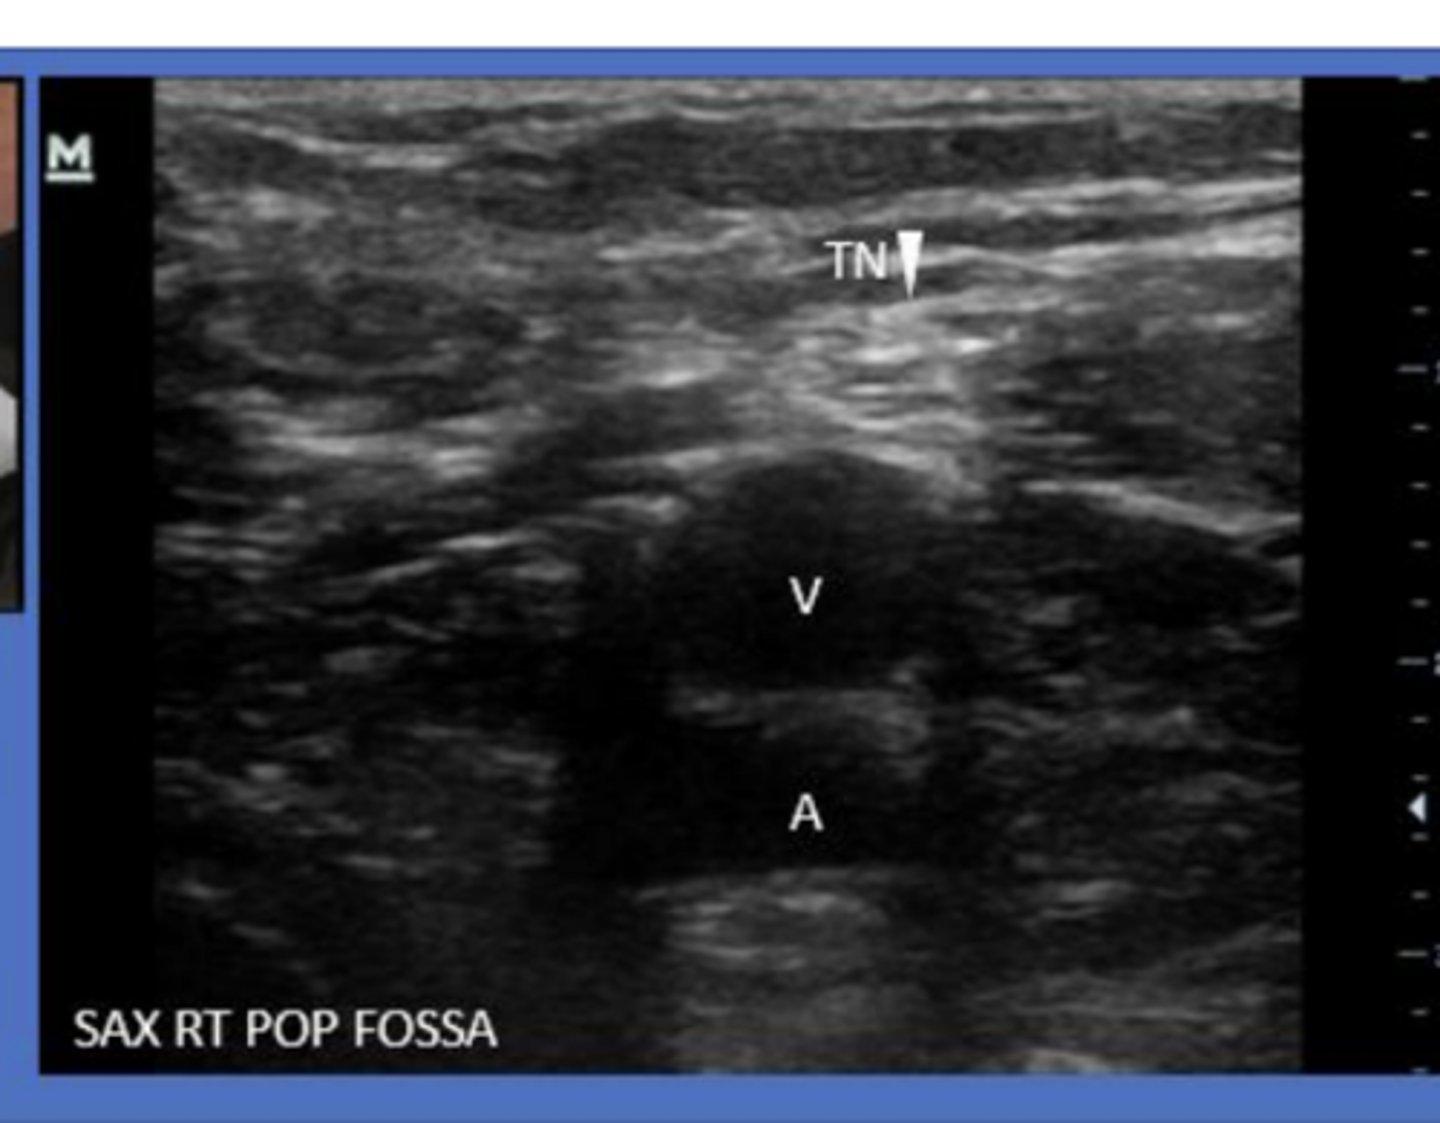

When scanning the vasculature in the posterior knee, what position should the patient be in?

prone with rolled towel under ankle OR with foot hanging off bed

What comprises the neurovascular bundle posterior to the knee?

popliteal artery/vein and tibial nerve

What is the clinical significance of the popliteal fossa?

site of DVT

site of baker's cysts

Inability to compress popliteal vein

Where do Baker's cysts usually originate in the popliteal fossa?